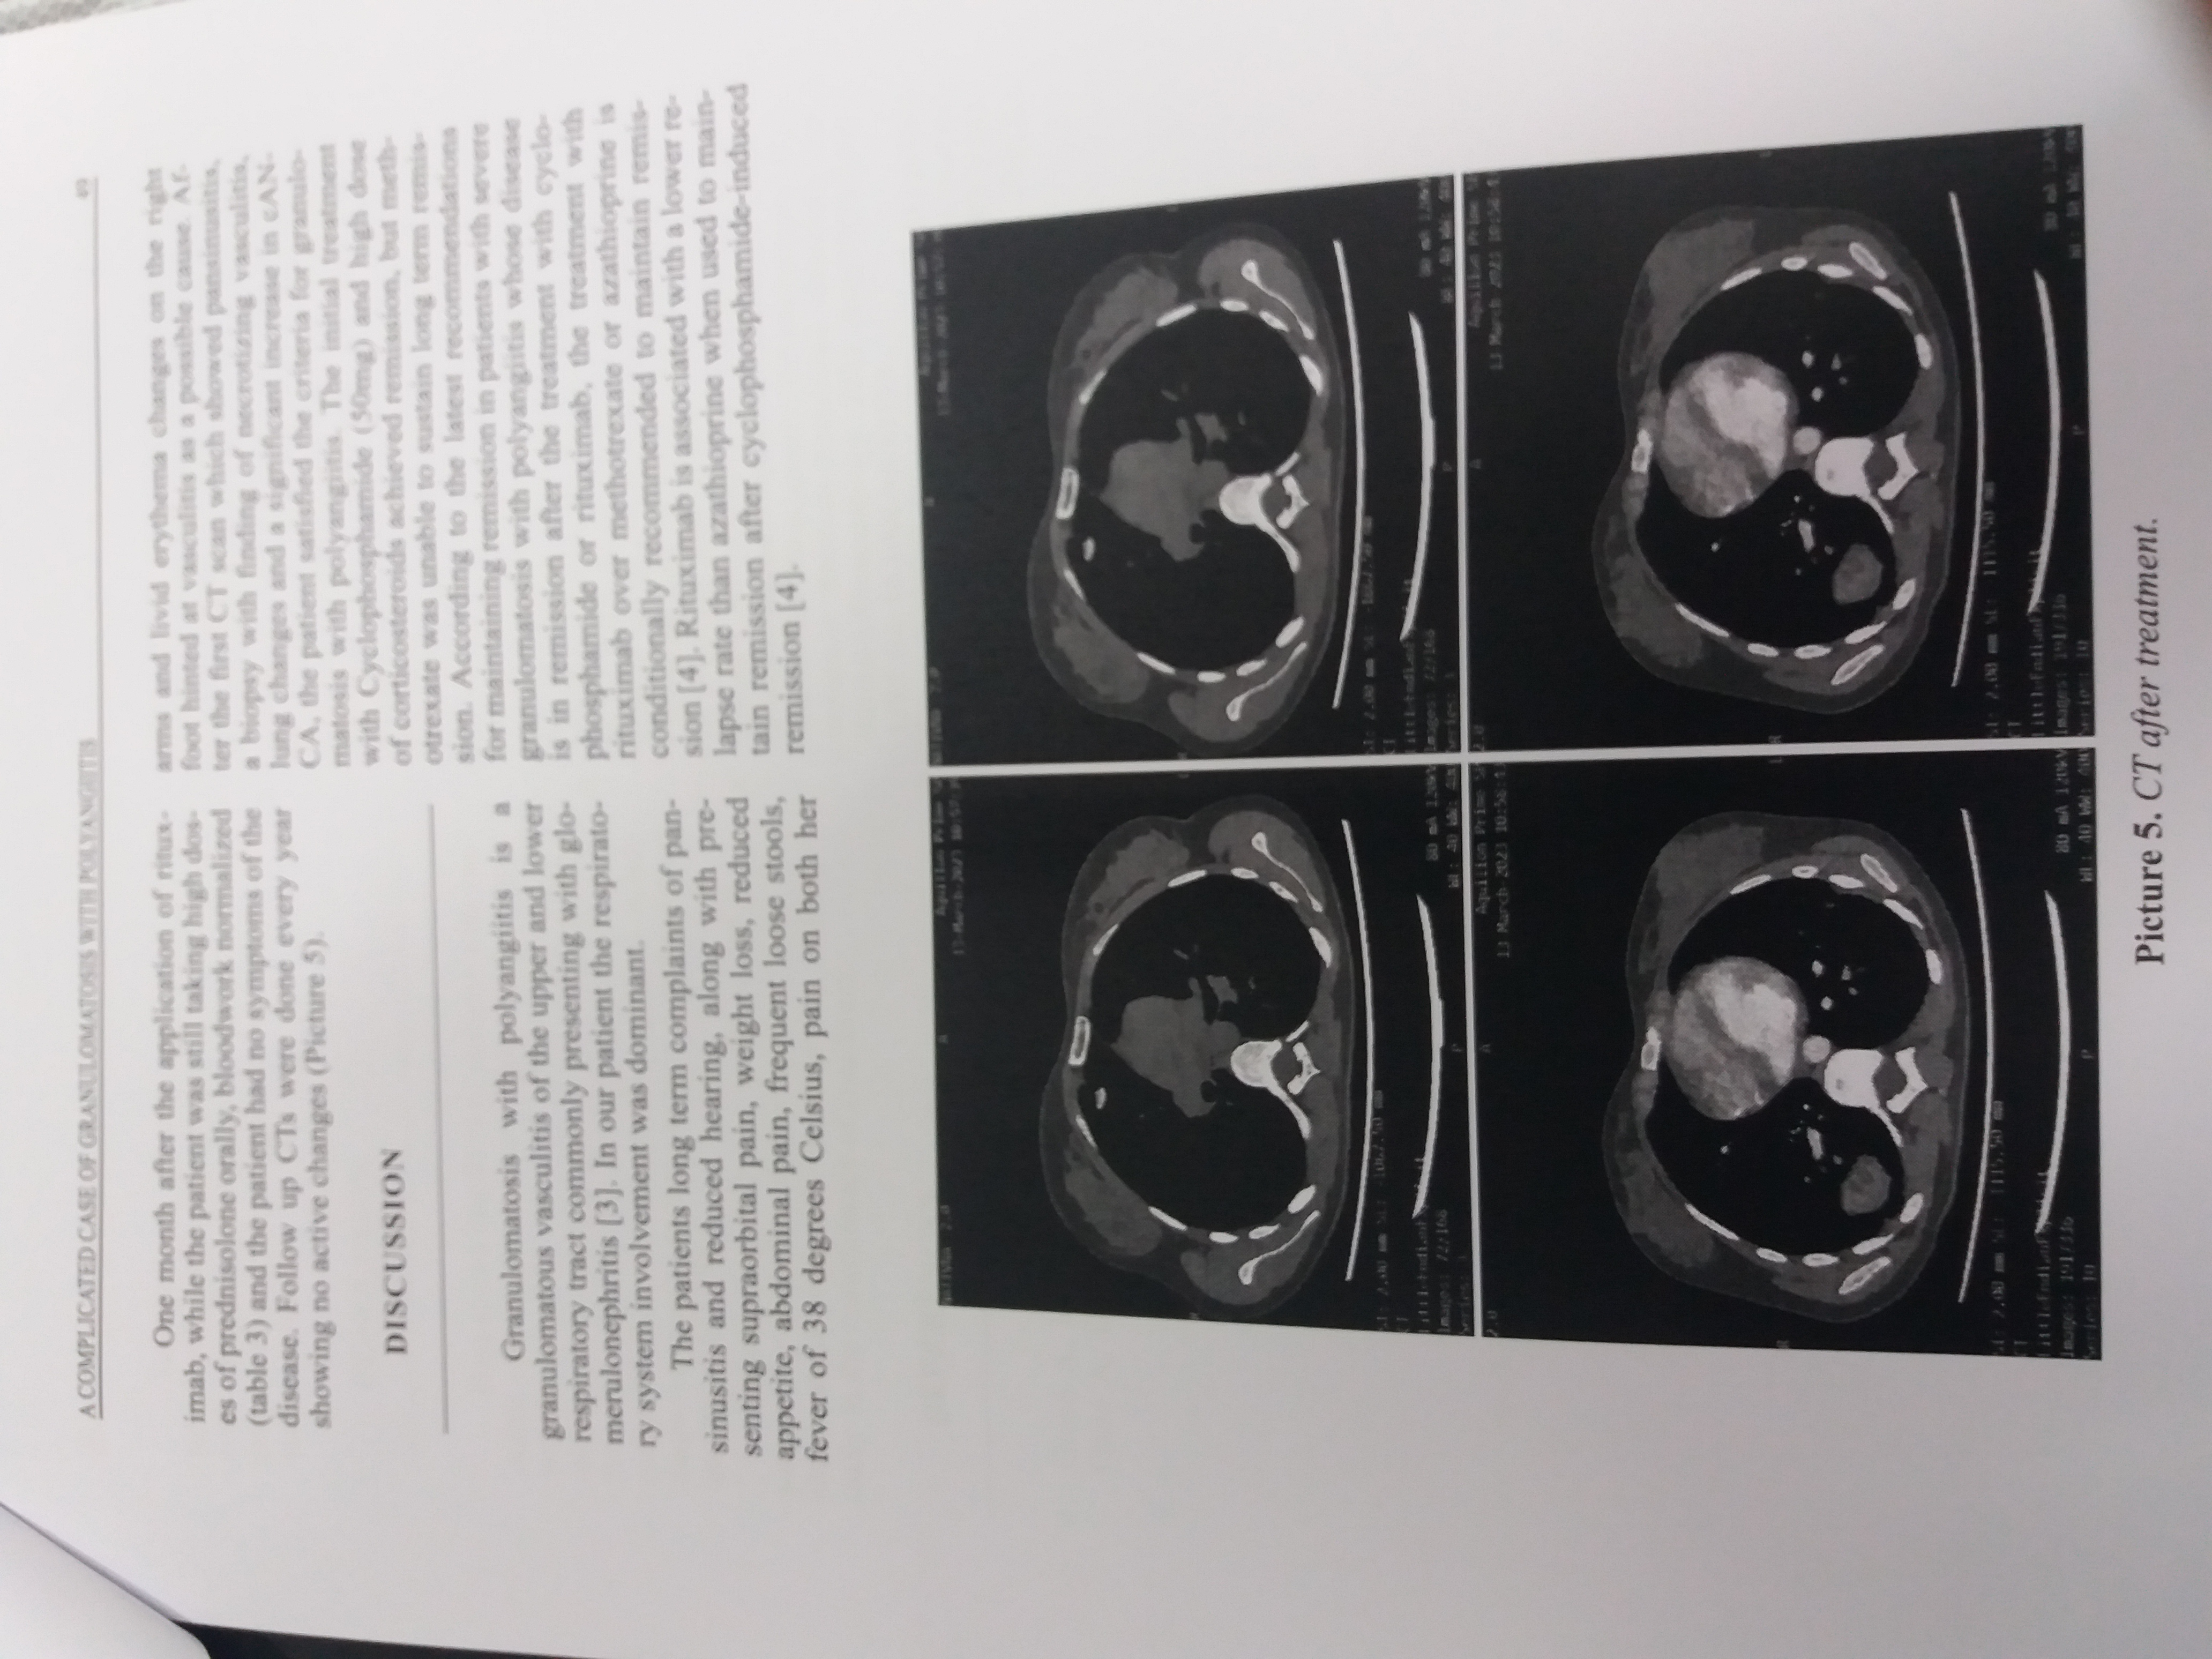

Issue Date: | јан-2025 | Publisher: | Macedonian Academy of Sciences and Arts/Walter de Gruyter GmbH | Journal: | Prilozi (Makedonska akademija na naukite i umetnostite. Oddelenie za medicinski nauki) | Abstract: | Granulomatosis with polyangiitis, formerly known as Wegener's granulomatosis, is a condition often presenting with granulomatous vasculitis of both the upper and lower respiratory tracts together with glomerulonephritis. Here we present a case of a 17-year-old female patient, who presented with symptoms of pansinusitis with other symptoms gradually following. She was treated with cyclophosphamide which was later switched to rituximab and is now in remission. | URI: | http://hdl.handle.net/20.500.12188/34377 | ISSN: | 1857-9345 | DOI: | 10.2478/prilozi-2025-0005 |